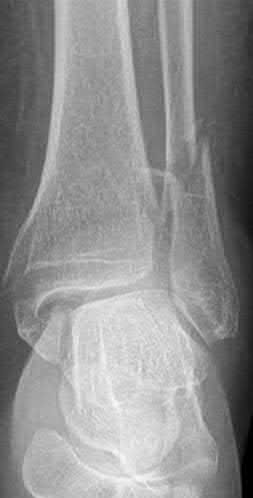

A 28-year-old male sustains a severe hyper-dorsiflexion injury to his ankle in a motor vehicle accident, resulting in a Hawkins Type III talar neck fracture. Which of the following arteries provides the predominant blood supply to the body of the talus, placing it at significant risk for avascular necrosis in this injury?

Correct Answer: Artery of the tarsal canal

Explanation:

The artery of the tarsal canal, which is a branch of the posterior tibial artery, provides the dominant blood supply to the talar body. In a Hawkins Type III fracture (talar neck fracture with subtalar and tibiotalar dislocation), the blood supply from the artery of the tarsal canal, the artery of the sinus tarsi, and capsular vessels are disrupted, leading to an avascular necrosis (AVN) rate approaching 100%.